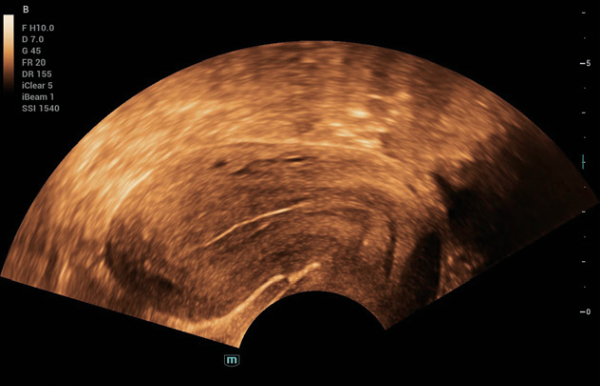

Solu??es abrangentes de imagens com tecnologia ZST+

A plataforma ZST+ ÃĐ uma inova??o extraordinÃĄria, representando a evolu??o do ultrassom. Transformando as mÃĐtricas de ultrassom: da forma??o convencional do feixe ao processamento baseado em dados de canais. Supera a limita??o de compensa??o tradicional entre resolu??o espacial, resolu??o temporal e uniformidade de tecido, oferecendo qualidade de imagem excepcional para solu??es de imagem infinitas com melhorias inigualÃĄveis.